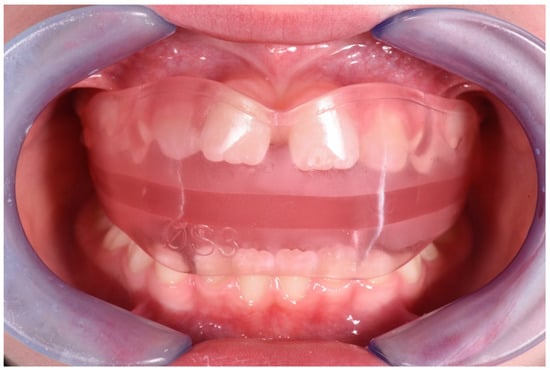

3.1. Clinical Case #1

3.2. Clinical Case #2

3.3. Clinical Case #3

3.4. Clinical Case #4